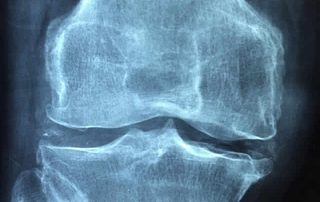

¿Qué es una dislocación del hombro? Un hombro dislocado ocurre cuando la bola del hueso de la parte superior de su brazo (cabeza del húmero) es forzada completamente fuera de su posición normal en el "encaje" del hombro (la glenoide). Una primera dislocación del